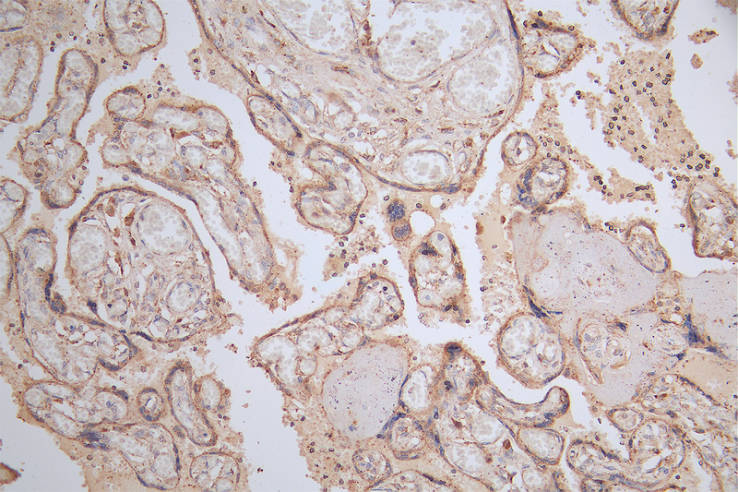

IHC image of CSB-RA566370A0HU diluted at 1:50 and staining in paraffin-embedded human placenta tissue performed on a Leica BondTM system. After dewaxing and hydration, antigen retrieval was mediated by high pressure in a citrate buffer (pH 6.0). Section was blocked with 10% normal goat serum 30min at RT. Then primary antibody (1% BSA) was incubated at 4°C overnight. The primary is detected by a Goat anti-rabbit polymer IgG labeled by HRP and visualized using 0.15% DAB.